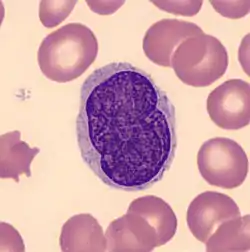

A histological view of Lutzner cells surrounded by erythrocytes in a blood smear. | |

Lutzner cells were discovered by Marvin A. Lutzner, Lucien-Marie Pautrier, and Albert Sézary. These cells are described as the smaller forms of Sézary cells, or Sézary-Lutzner[1] cells, and the two variants are recognised as being morphologically different. Aggregates of these cells in mycosis fungoides are known as a Pautrier's microabscesses. They are a form of T-lymphocytes that has been mutated[2] This atypical form of T-lymphocytes contains T-cell receptors on the surface and is found in both the dermis and epidermis layers of the skin. Since Lutzner cells are a mutated form of T-lymphocytes, they develop in bone marrow and are transported to the thymus is order to mature.[3] The production and maturation stages occur before the cell has developed a mutation. Lutzner cells can form cutaneous T-cell lymphoma, which is a form of skin cancer.[4]

Lymphocytes are white blood cells that form from a blood stem cell, hemocytoblast, in bone marrow and travel to other parts of the body, normally specific lymphoid tissues, to mature. After being produced, the stem cell differentiates into lymphoid stem cells. Then, T-lymphocytes further mature and differentiate into lymphoblasts when the hormone thymosin is secreted from the thymus. Finally, specialized immune cells, B cells and T cells, and nonspecialized immune cells, nature killer cells, are created from the lymphoblasts. This process is referred to as Leukopoiesis. Lutzner cells are an atypical form of T-cell lymphocytes and are normally CD4+.[3] Lutzner cells develop because of clonal gene rearrangements in the T-cell receptor or antibody. This rearrangement occurs early in the differentiation process and creates novel T-cell receptors that mimic the structure of normal antibodies but are not able to function properly. This mutated form contains an enfolded nuclear membrane and has a cerebriform shape, resembling the shape and folds of the brain.[5] Lutzner cells can be best seen through electron microscopy because it is able to show the 3-D structure of the cell.

Lutzner cells are bigger than normal lymphocytes and contain extensive folding in their membrane. They are described at being cerebriform in shape, and can be diploid or tetraploid. It also contains a large nucleus with a minimum cytoplasm. Lutzner cells are more predominant in Mycosis Fungoides, but are also found in Sézary Syndrome.[7]